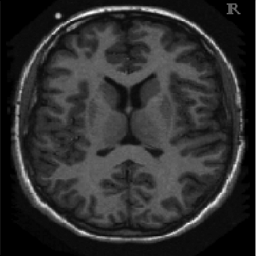

4.1. Uniform Gaussian noise

In this first experiment, we consider the denoising problem with brain scan images. The first set consists of images of pixels and Gaussian noise with zero mean and variance . The original and noisy images are shown in Figure 4.1. The domain decomposition-semismooth Newton algorithms run with the parameter values , , and . The results are shown in Figure 4.2. From the surface representation of , we can observe that is continuous and its shape is related to the one of the original image. In particular, the regularization is stronger in homogeneous regions in the image, and weaker where the image intensity undergoes variations on a smaller scale.

In Table 4.1 the performance of the different methods is compared. For all of them, only the first 2 domain decomposition iterations were considered. The total number of SSN iterations differ at most by one. The impact of the domain decomposition method becomes clear when comparing the computing times of the methods, corresponding to one, two and four subdomains. The computing time is significantly reduced. The effect of the optimized transmission conditions can be realized when comparing the gap between subdomains, which is much lower in the case of optimized transmission conditions () than in the standard Schwarz method ().